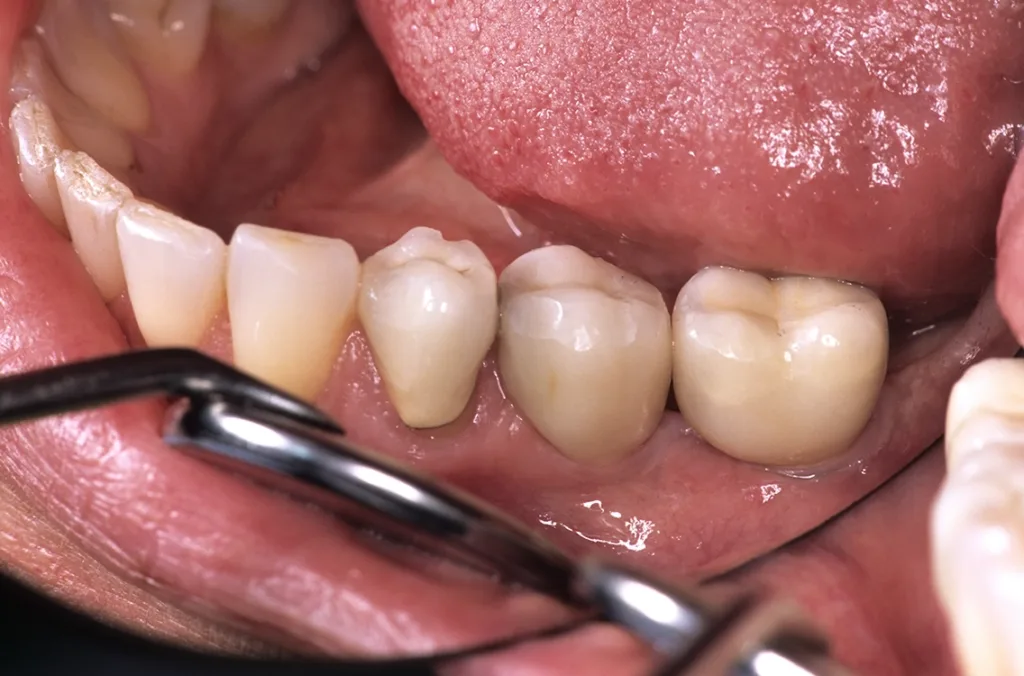

- Anatomie: Behandelte fortgeschrittene Parodontalerkrankungen sind klinisch stabil, zeigen aber in den implantatrelevanten anatomischen Knochenabschnitten (bukkale Lamellen, interapproximales Septum) weitere Abbauvorgänge durch Entzündung (Abb. 1 und 2) [1].

Daraus resultiert ein zweizeitiges Vorgehen mit (i) Entfernung prognostisch unsicherer Zähne, (ii) parodontaler Zieltherapie zur Sicherung des Restzahnbestandes, ergänzt durch (iii) mikrochirurgische Revision tiefer Resttaschen vor Implantation zum weiteren Entzündungsschutz (Abb. 3 und 4). Die Implantatplanung bleibt vorläufig. Ein definitiver Kostenvoranschlag wird erst nach funktioneller Entlastung und digitaler Beurteilung der Implantatknochenanatomie erstellt.